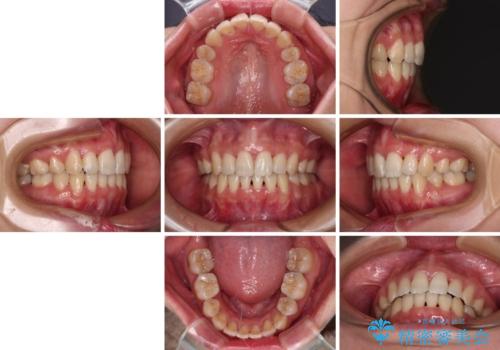

Eラインを改善したい ハーフリンガルによる抜歯矯正

- 口元の突出感を気にして来院された患者様です。

上下左右の第一小臼歯4本を抜歯して口元を下げる治療計画としました。

舌の突出癖が強く、口元を引っ込める力に拮抗してしまい、抜歯スペースを閉じるまでに時間がかかりました。

また途中出産もありましたが、無事に治療を終えることができました。